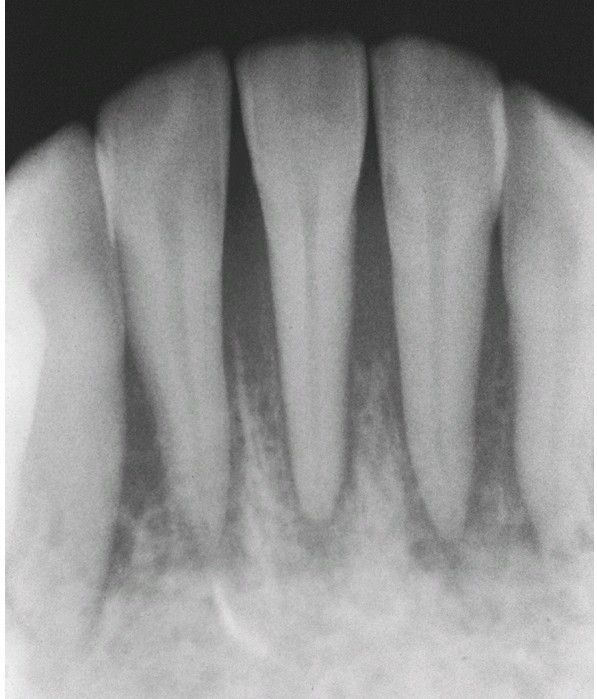

Periapical radiograph showing widening of the periodontal ligament spaces.